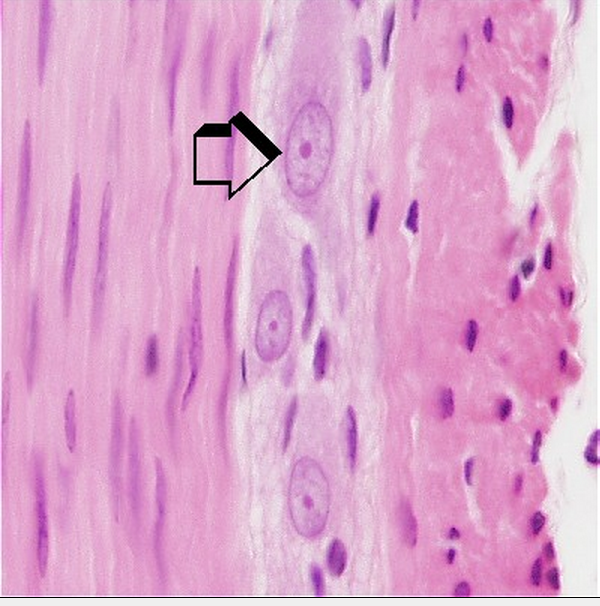

Q

What type of cell is this?

A

Ganglion Cell